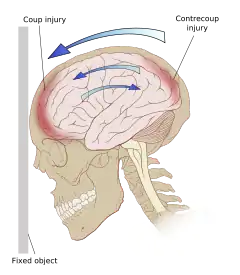

Even in the absence of an impact, significant acceleration or deceleration of the head can cause TBI; however in most cases, a combination of impact and acceleration is probably to blame.[37] Forces involving the head striking or being struck by something, termed contact or impact loading, are the cause of most focal injuries, and movement of the brain within the skull, termed noncontact or inertial loading, usually causes diffuse injuries.[20] The violent shaking of an infant that causes shaken baby syndrome commonly manifests as diffuse injury.[67] In impact loading, the force sends shock waves through the skull and brain, resulting in tissue damage.[37] Shock waves caused by penetrating injuries can also destroy tissue along the path of a projectile, compounding the damage caused by the missile itself.[23]

Damage may occur directly under the site of impact, or it may occur on the side opposite the impact (coup and contrecoup injury, respectively).[66] When a moving object impacts the stationary head, coup injuries are typical,[68] while contrecoup injuries are usually produced when the moving head strikes a stationary object.[69]